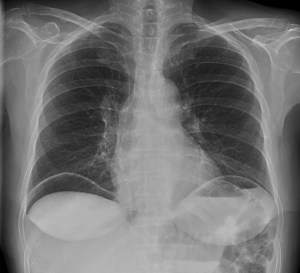

Paciente con diarrea y vómitos y dolor abdominal intenso. Antecedentes de fibrilación auricular. Analítica con discreta leucocitosis.

Se sospecha Isquemia intestinal. Veamos las pruebas complementarias de imagen:

En conclusión, estamos ante un cuadro de posible isquemia intestinal perforada, de ahí el neumoperitoneo.